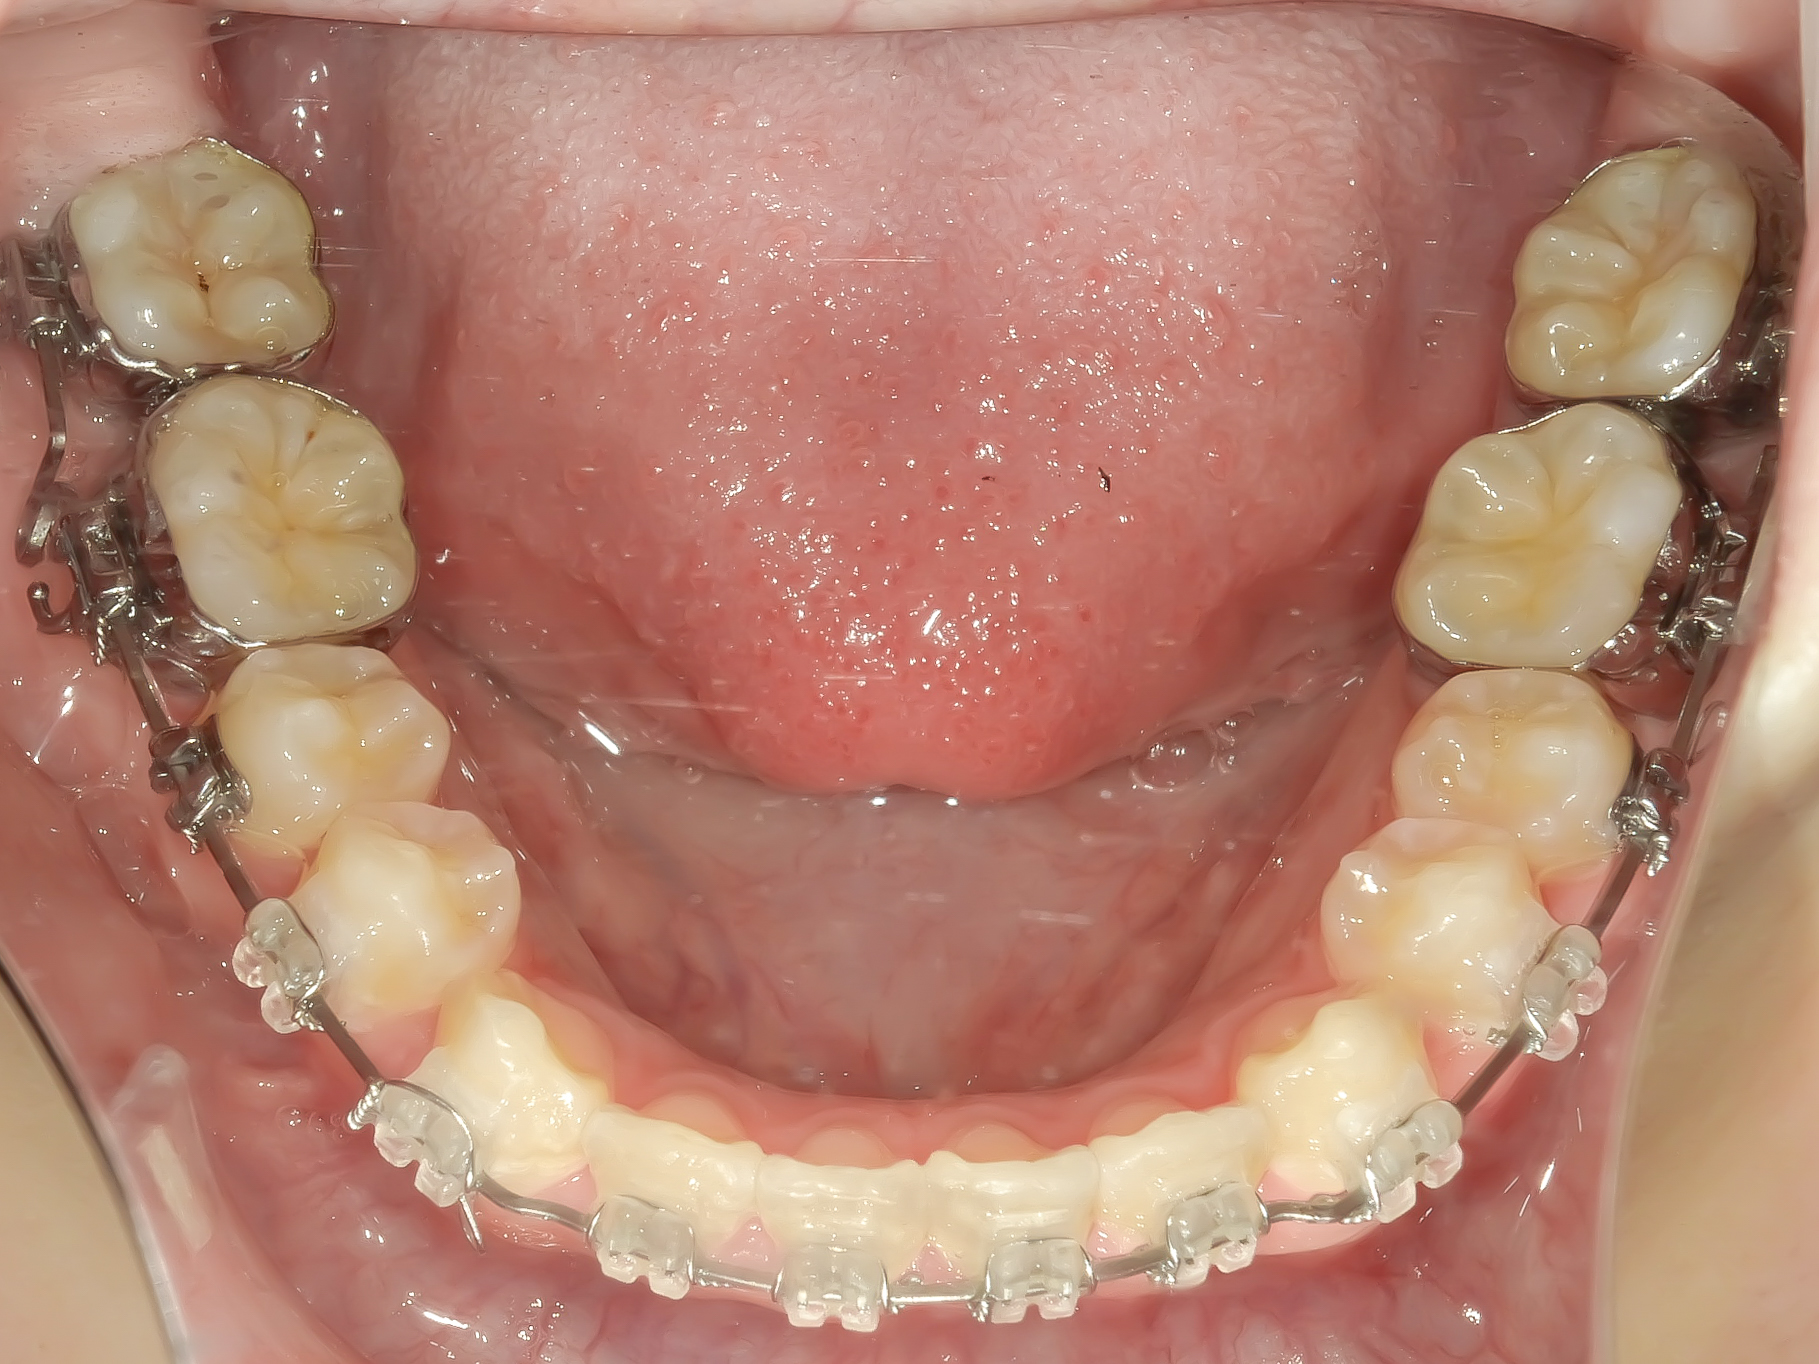

After

下顎にもワイヤーが入り、きれいに並んできています。

下顎も叢生がなくなりました。

正面から見てもきれいに並んでおり、上下の真ん中の線も一致しました。